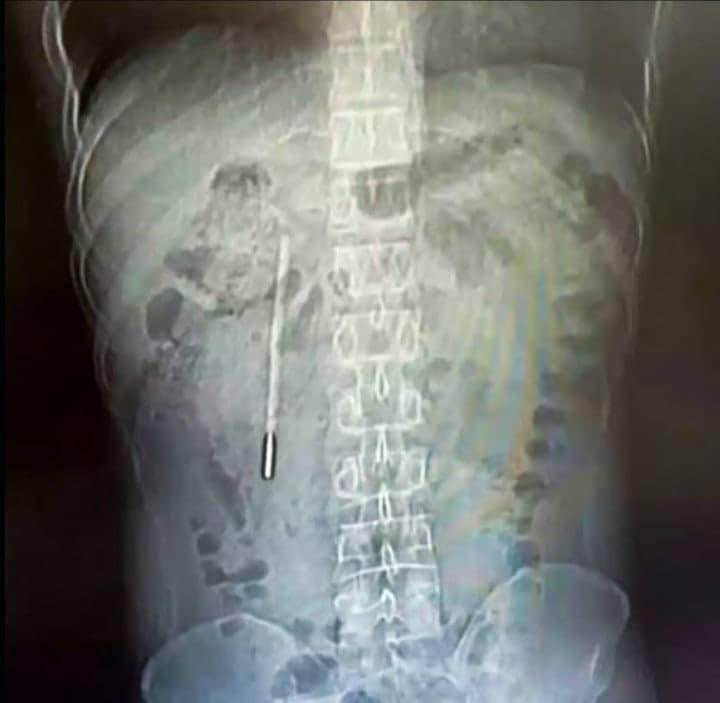

복통으로 병원 찾은 30대 남성, 뱃속에서 20년 전 삼킨 '수은 온도계' 발견

환자는 어린 시절 부모님께 혼날까 봐 삼킨 사실을 숨겼고, 20년간 별다른 증상이 없어 잊고 지냈습니다.

체온계는 내시경으로 20분 만에 제거되었고, 다행히 파손되거나 수은이 유출되지 않았습니다.